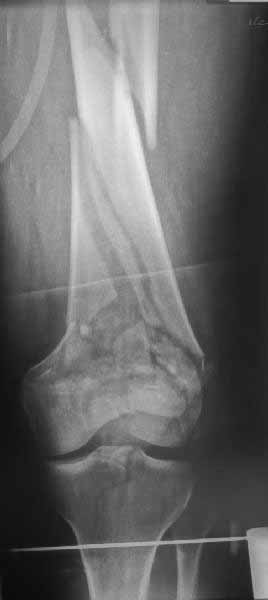

Однако в случае, представленном Константином Никитиным, не может быть применён ни ретроградный ни антеградный остеосинтез. Причина - нереально выполнить вышеуказанные необходимые требования, касающиеся дистальных блокирующих винтов. Из-за низкого перелома латерального мыщелка (перелом Hoffa) невозможно через него провести хотя бы 2 блокирующих винта, поскольку линия перелома мыщелка расположена либо на уровне верхушки межмыщелковой ямки либо незначительно проксимальнее. Поэтому авторам, с моей точки зрения, необходимо прислушаться к рекомендациям Джолдаса.

наружный мыщелок не дорепонироавн - это приводит к вальгусной деформации оси коленного сустава, очень критично для последующей функции.